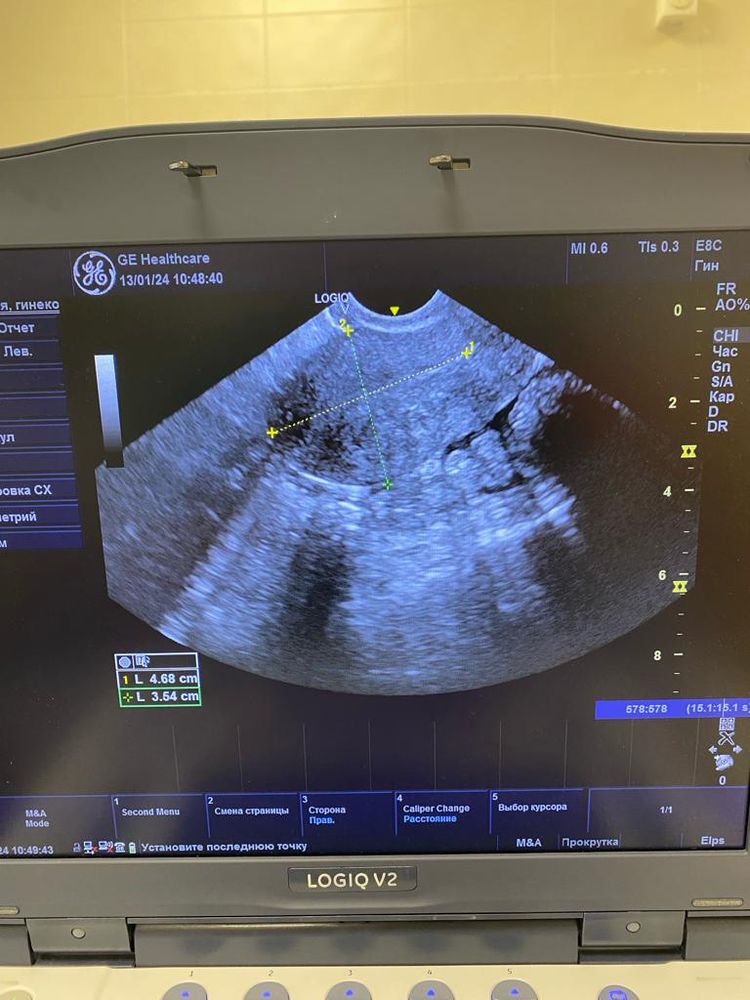

Юлия , Изображение Изображение Изображение Изображение Изображение

Ольга, по этим снимкам овуляция не вот вот. А до нее еще как минимум неделя от этого УЗИ. Фолликулы до 10 мм. И нет доминанта

Ольга, не нужны снимки, нужен протокол УзИ. Описание яичников, срез, ДФ, эндометрий. Врач узи в нескольких проекция смотрит. Я как врач, на этих снимках не вижу ДФ, фолликулы до 10 мм.. Поэтому вообще-то говорить что была овуляция сложно. Сейчас делать УЗИ нет смысла. Ждите менструацию, она начнется со дня на день. Делайте УЗи уже в след цикле в динамике, по мере роста ДФ и подтверждайте овуляцию через 7 дней после ее наступления и берите протоколы УЗИ. Сейчас мы с Вами просто гадаем на кофейной гуще.